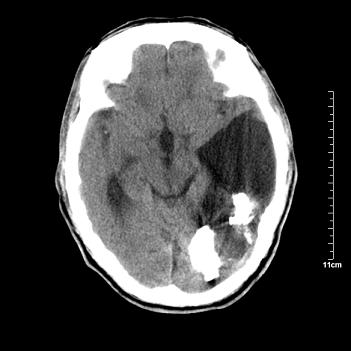

男性患者,72岁,近两天头晕来我院就诊。 因患者血压太高而未做增强,建议病人去市医院做mri检查。等得到mri随访结果再公布给大家。 测及左颞顶枕叶病灶ct值分别为5hu 30hu 729hu。

考虑左侧颞顶枕叶少突胶质细胞瘤。 今天随访患者手术病理结果 病理回报为胶质瘤2级 钙化

左侧颞顶枕叶大片状低密度影,呈均一水样密度,边界清楚,病灶边缘不规则片状钙化,左侧脑室后角扩大,中线结构未见移位,综合来看不像肿瘤,软化灶,钙化不好解释

左侧颞顶枕叶巨大囊性病灶,灶内见小片实性区且灶内及灶周围大量团块状钙化影,灶周水肿少.左侧室枕角内见环形钙化,可见较清晰前壁,钙化与室壁似有间隙.

考虑1寄生虫病2表皮样囊肿钙化3血管畸形,其他不排

囊变明显,钙化明显,部分实性组织,轻度占位,左侧脑室受压---考虑 少突胶质细胞瘤,畸胎瘤,寄生虫病

今天追踪患者家属手术病理结果 病理回报为胶质瘤2级并钙化

病理回报为胶质瘤2级并钙化